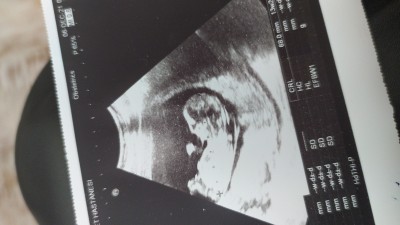

Anneler ve anne adayları biraz heyecanima verin bana erkek gibi geliyor ama.sizin içinize ne doğdu

Ben pipi gbi bişi görüyorum amaaaa

Erkek gibi hissettim